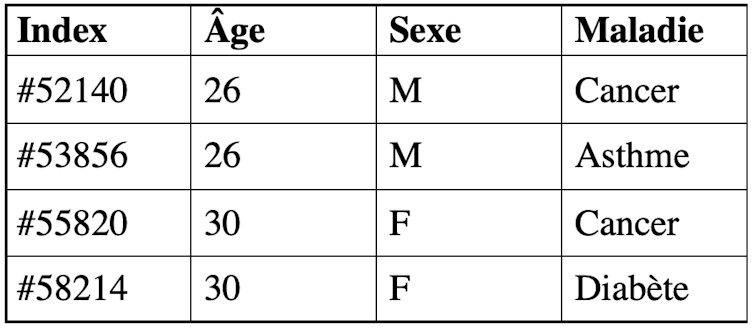

Sur le tableau ci-dessous, par exemple, K = 2 signifie qu’au moins 2 personnes ont les mêmes attributs âge et sexe, ainsi si un attaquant a connaissance qu’un individu de 26 ans de sexe masculin fait partie du jeu de données, il ne pourra pas établir de corrélation et savoir à quelle ligne correspond cet individu (#52140 ou #53856). Il ne pourra donc pas le réidentifier.

Plus K est grand, plus la méthode offre de garanties en termes de confidentialité. On notera que pour obtenir le résultat du 2-anonymat, il est possible d’appliquer une transformation par généralisation pour diminuer la précision d’une information, la date de naissance d’un individu devient par exemple son âge.

Pour empêcher l’attaque par inférence, qui vise à déduire par exemple de quelle maladie souffre un individu ou une catégorie d’individus, il existe la méthode de L-diversité, « L » étant un paramètre à fixer. Il s’agit de s’assurer que chaque groupe d’individus constitué suite au K-anonymat ne pointe pas vers une maladie unique, mais au moins L maladies possibles. Ainsi, dans l’exemple simple, l’attaquant ne pourra pas déduire qu’un individu de 26 ans de sexe masculin souffre d’une maladie précise, mais qu’il a soit un cancer, soit de l’asthme.